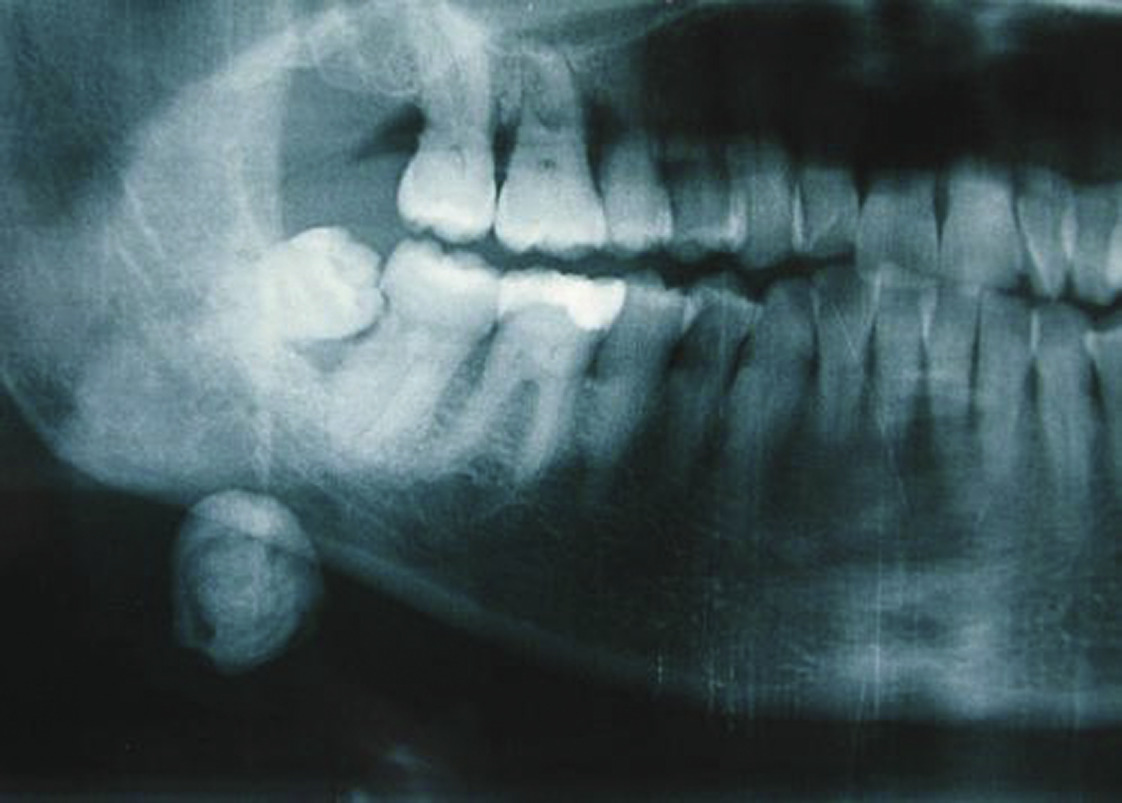

Le scanner

C’est un examen clé, de grande sensibilité et valeur localisatrice. C’est l’examen de choix. Il est le plus souvent effectué sans injection de produit de contraste. L’injection ne sera nécessaire qu’en cas de suspicion d’infection ou de tumeur (fig. 9).